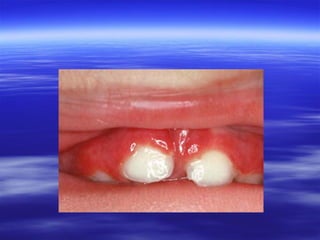

:Acute Antibiotic Stomatitis

 Overuse or topical oral use of antibiotics,

especially tetracycline, suppressing normal

competing oral flora.

 Clinically, the whole mucosa is red and

sore. Flecks of thrush may be present.

 Resolution may follow withdrawal of the

antibiotic but is accelerated by topical

antifungal treatment.